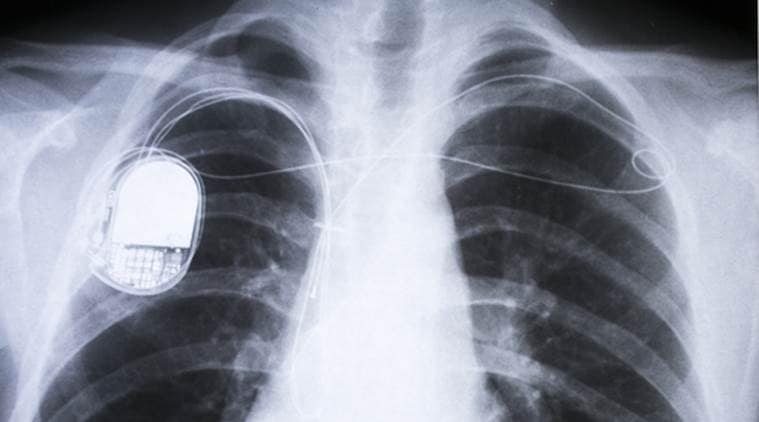

Millions of people rely on pacemakers, defibrillators and other live-saving implantable devices powered by batteries that need to be replaced every five to 10 years.

Millions of people rely on pacemakers, defibrillators and other live-saving implantable devices powered by batteries that need to be replaced every five to 10 years, they said. Those replacements require surgery which can be costly and create the possibility of complications and infections, according to the study published in the journal Advanced Materials Technologies.